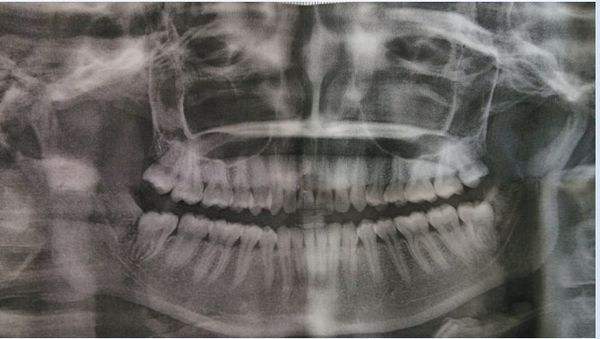

看到没,只有这样整整齐齐,根正苗也正,顺利长出来的智齿,才有可能逃过一劫。